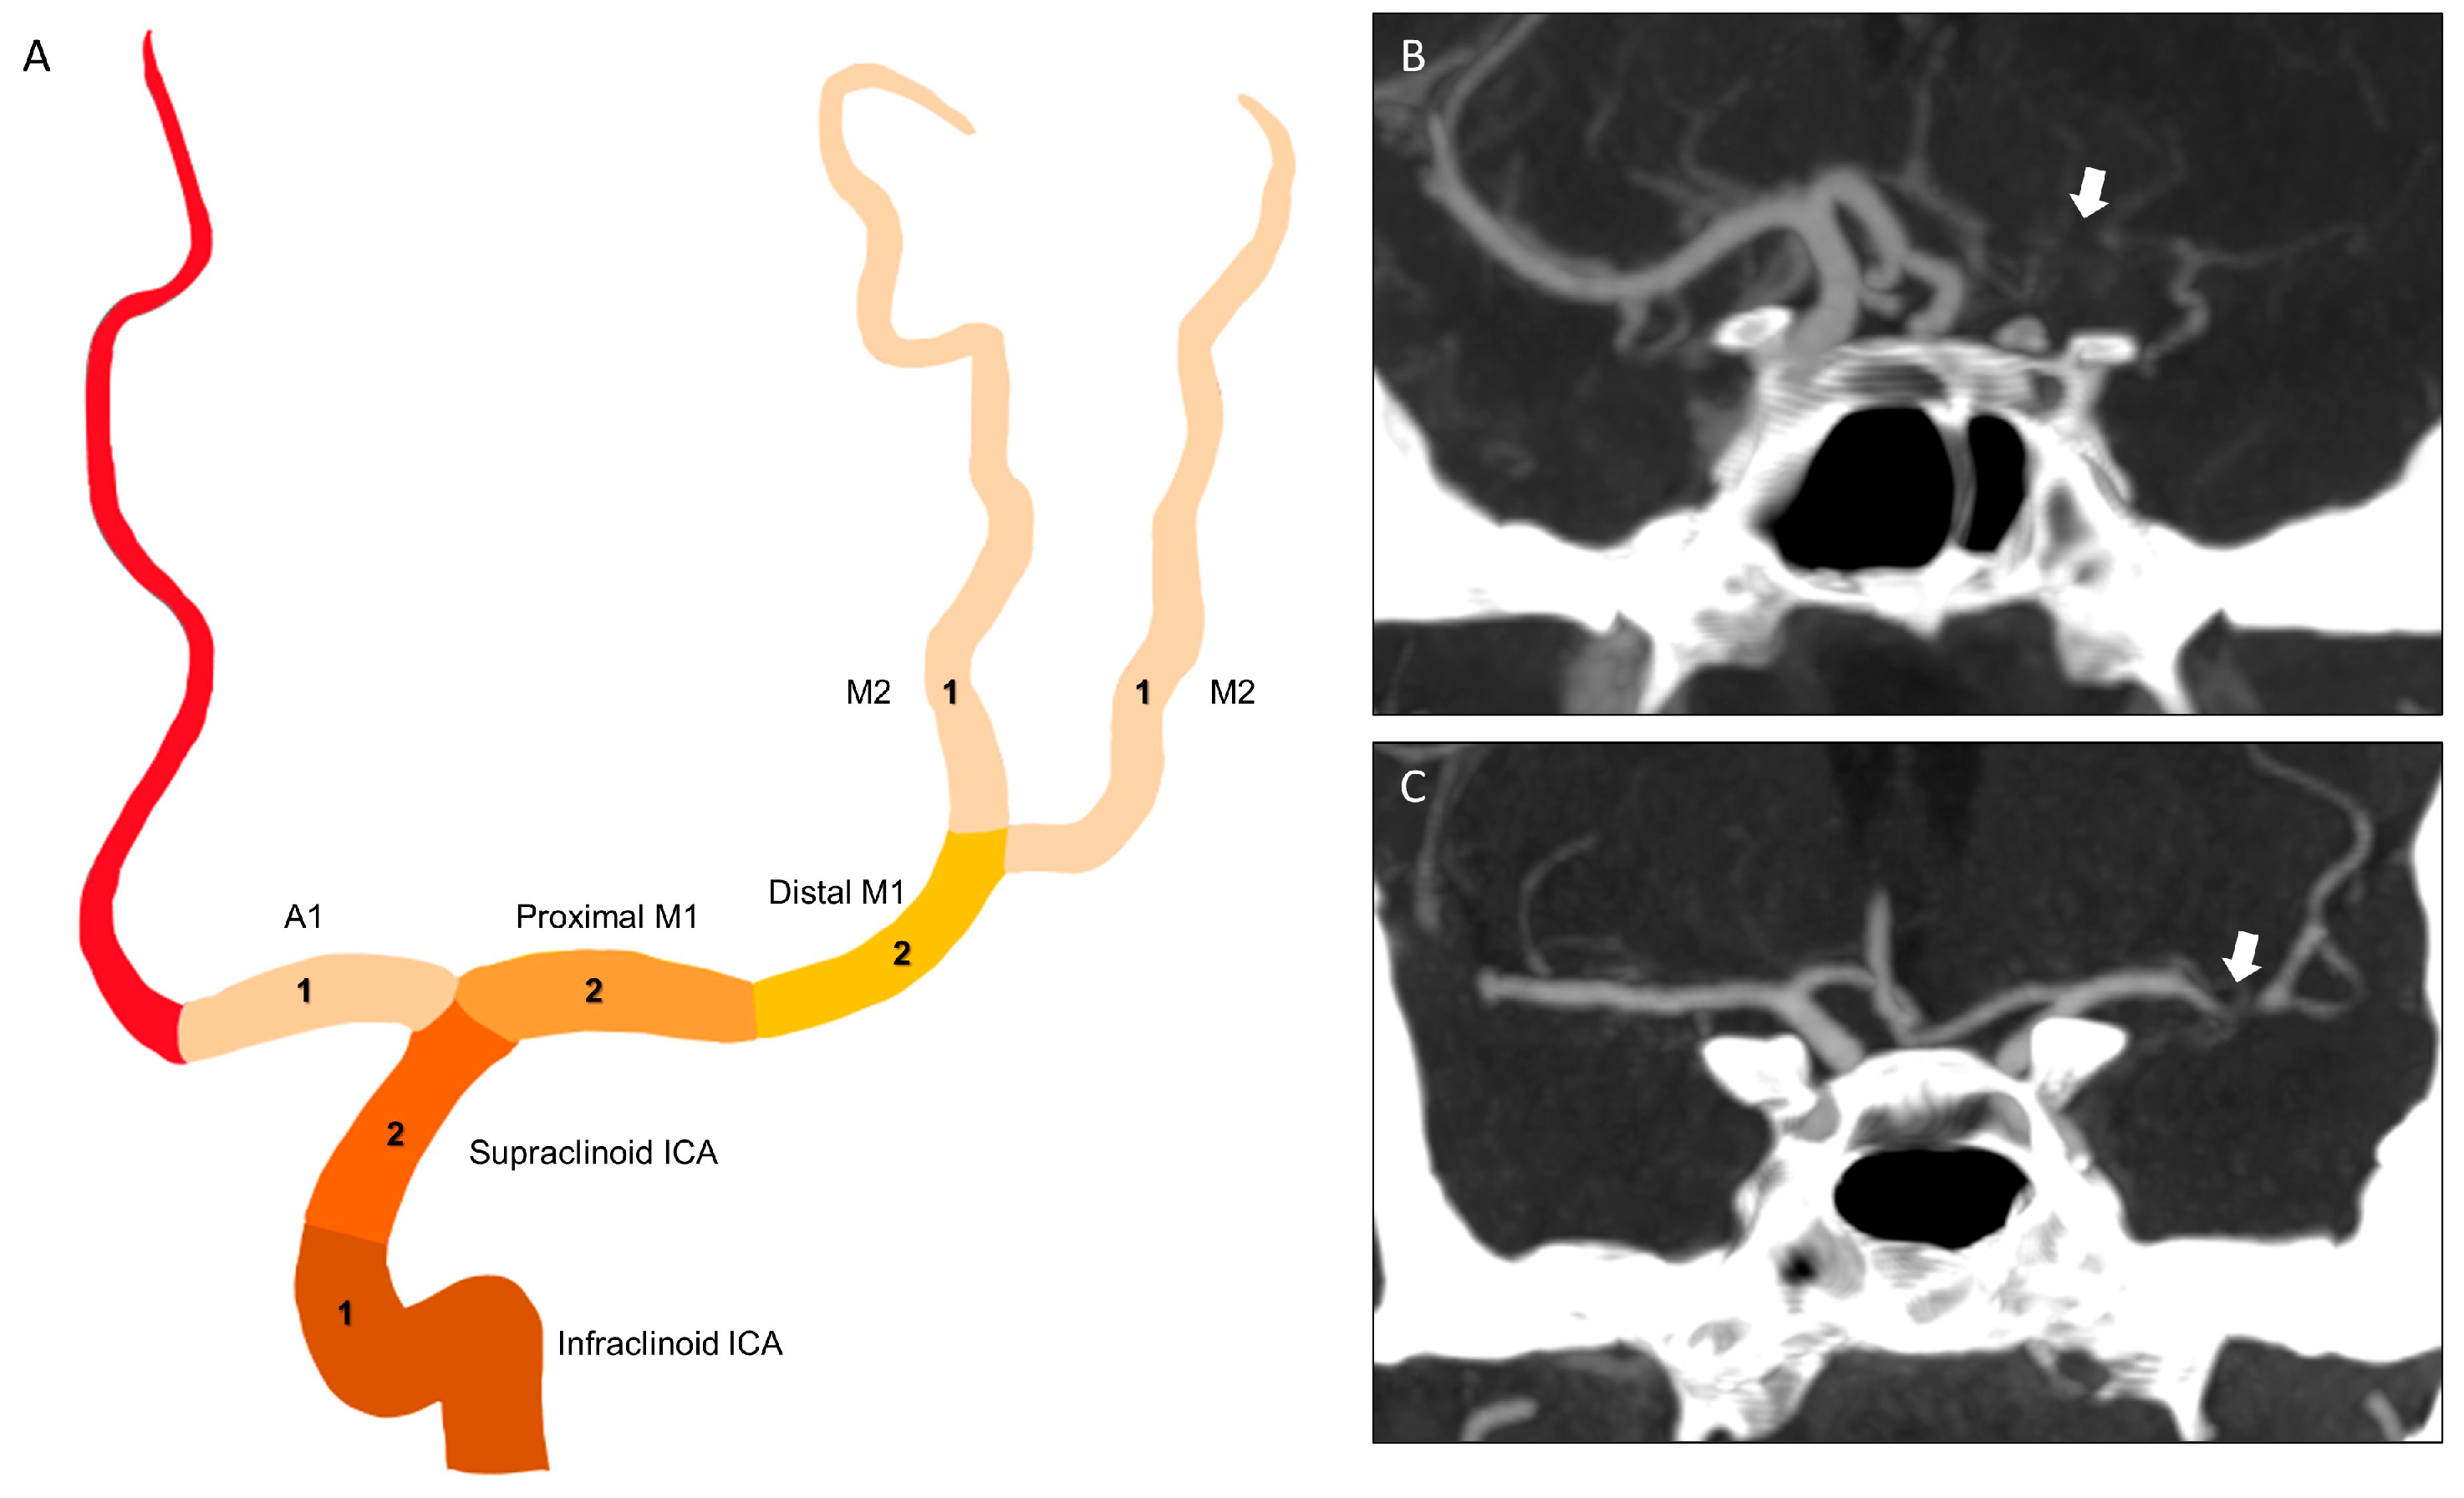

| CBS | clot burden score |

| CBV | cerebral blood volume |

| CTA | computed tomography angiography |

| CTP | computed tomography perfusion |

| ICA | internal carotid artery |